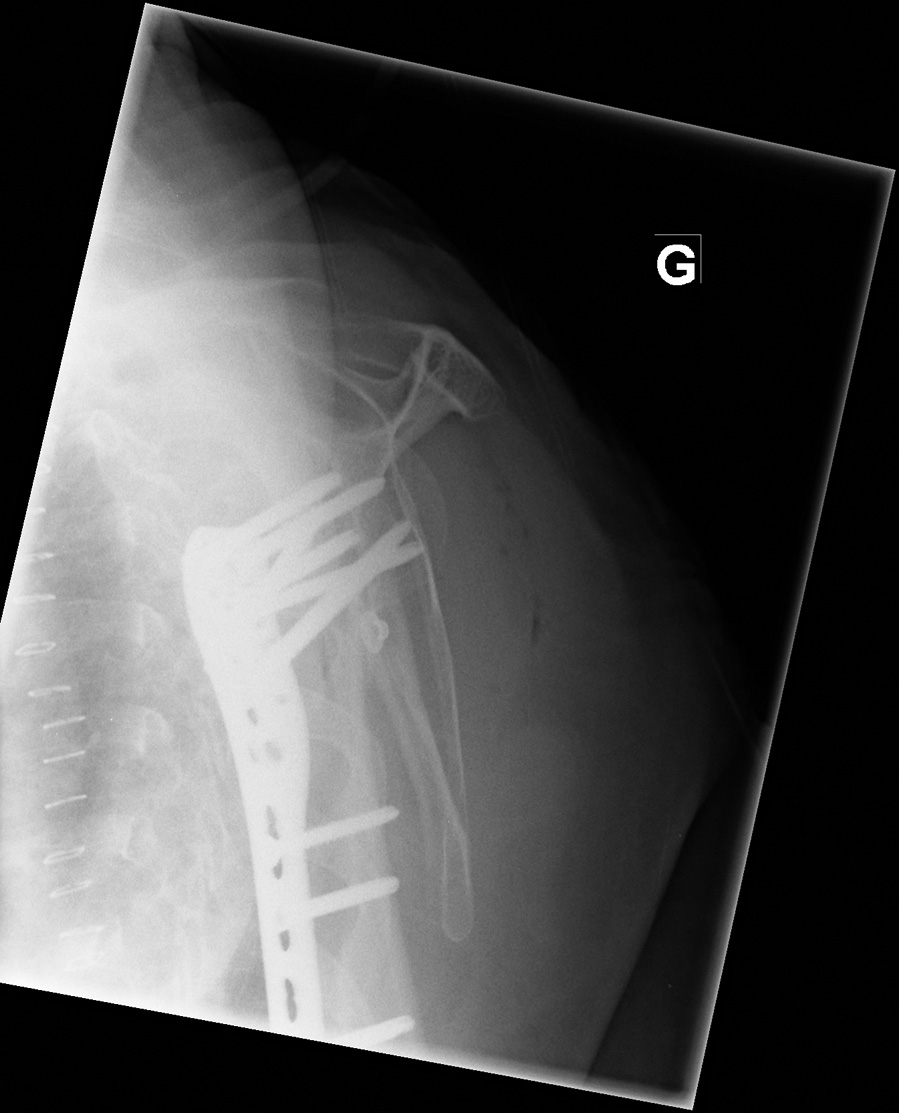

62-year-old female:

Shoulder pain following a fall from standing height on a hyperextended arm.

Philos plate

Proximal humerus fracture

Plate and screws

Open reduction of a proximal humerus fracture and internal fixation with a Philos plate. Multiple screws provide enhanced stability.

Metallic staples

Metallic staples for skin closure.

Transscapular view (Neer, "Y" or lateral view of the shoulder)

• Anteroposterior (internal rotation)

• Transscapular view (Neer, "Y" or lateral view of the shoulder)